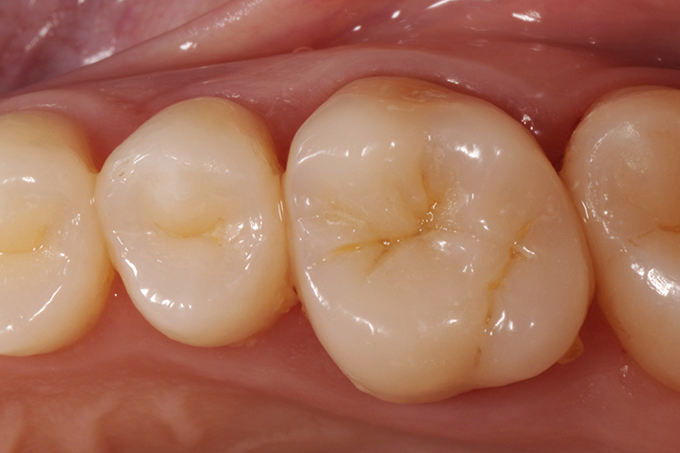

Overlay immediately after cementation with natural teeth still dehydrated.

Check-up - 15 days after successful reconstruction.